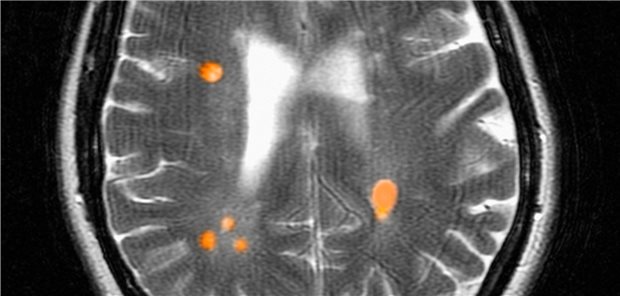

Die Erkrankung im Blick: Multiple Sklerose in der Magnetresonanzangiografie bei einer 42-jährigen Frau.

© Image Source / mauritius images

Stufenschema gilt nicht mehr

Bei Multipler Sklerose mit Eskalation nicht lange zögern